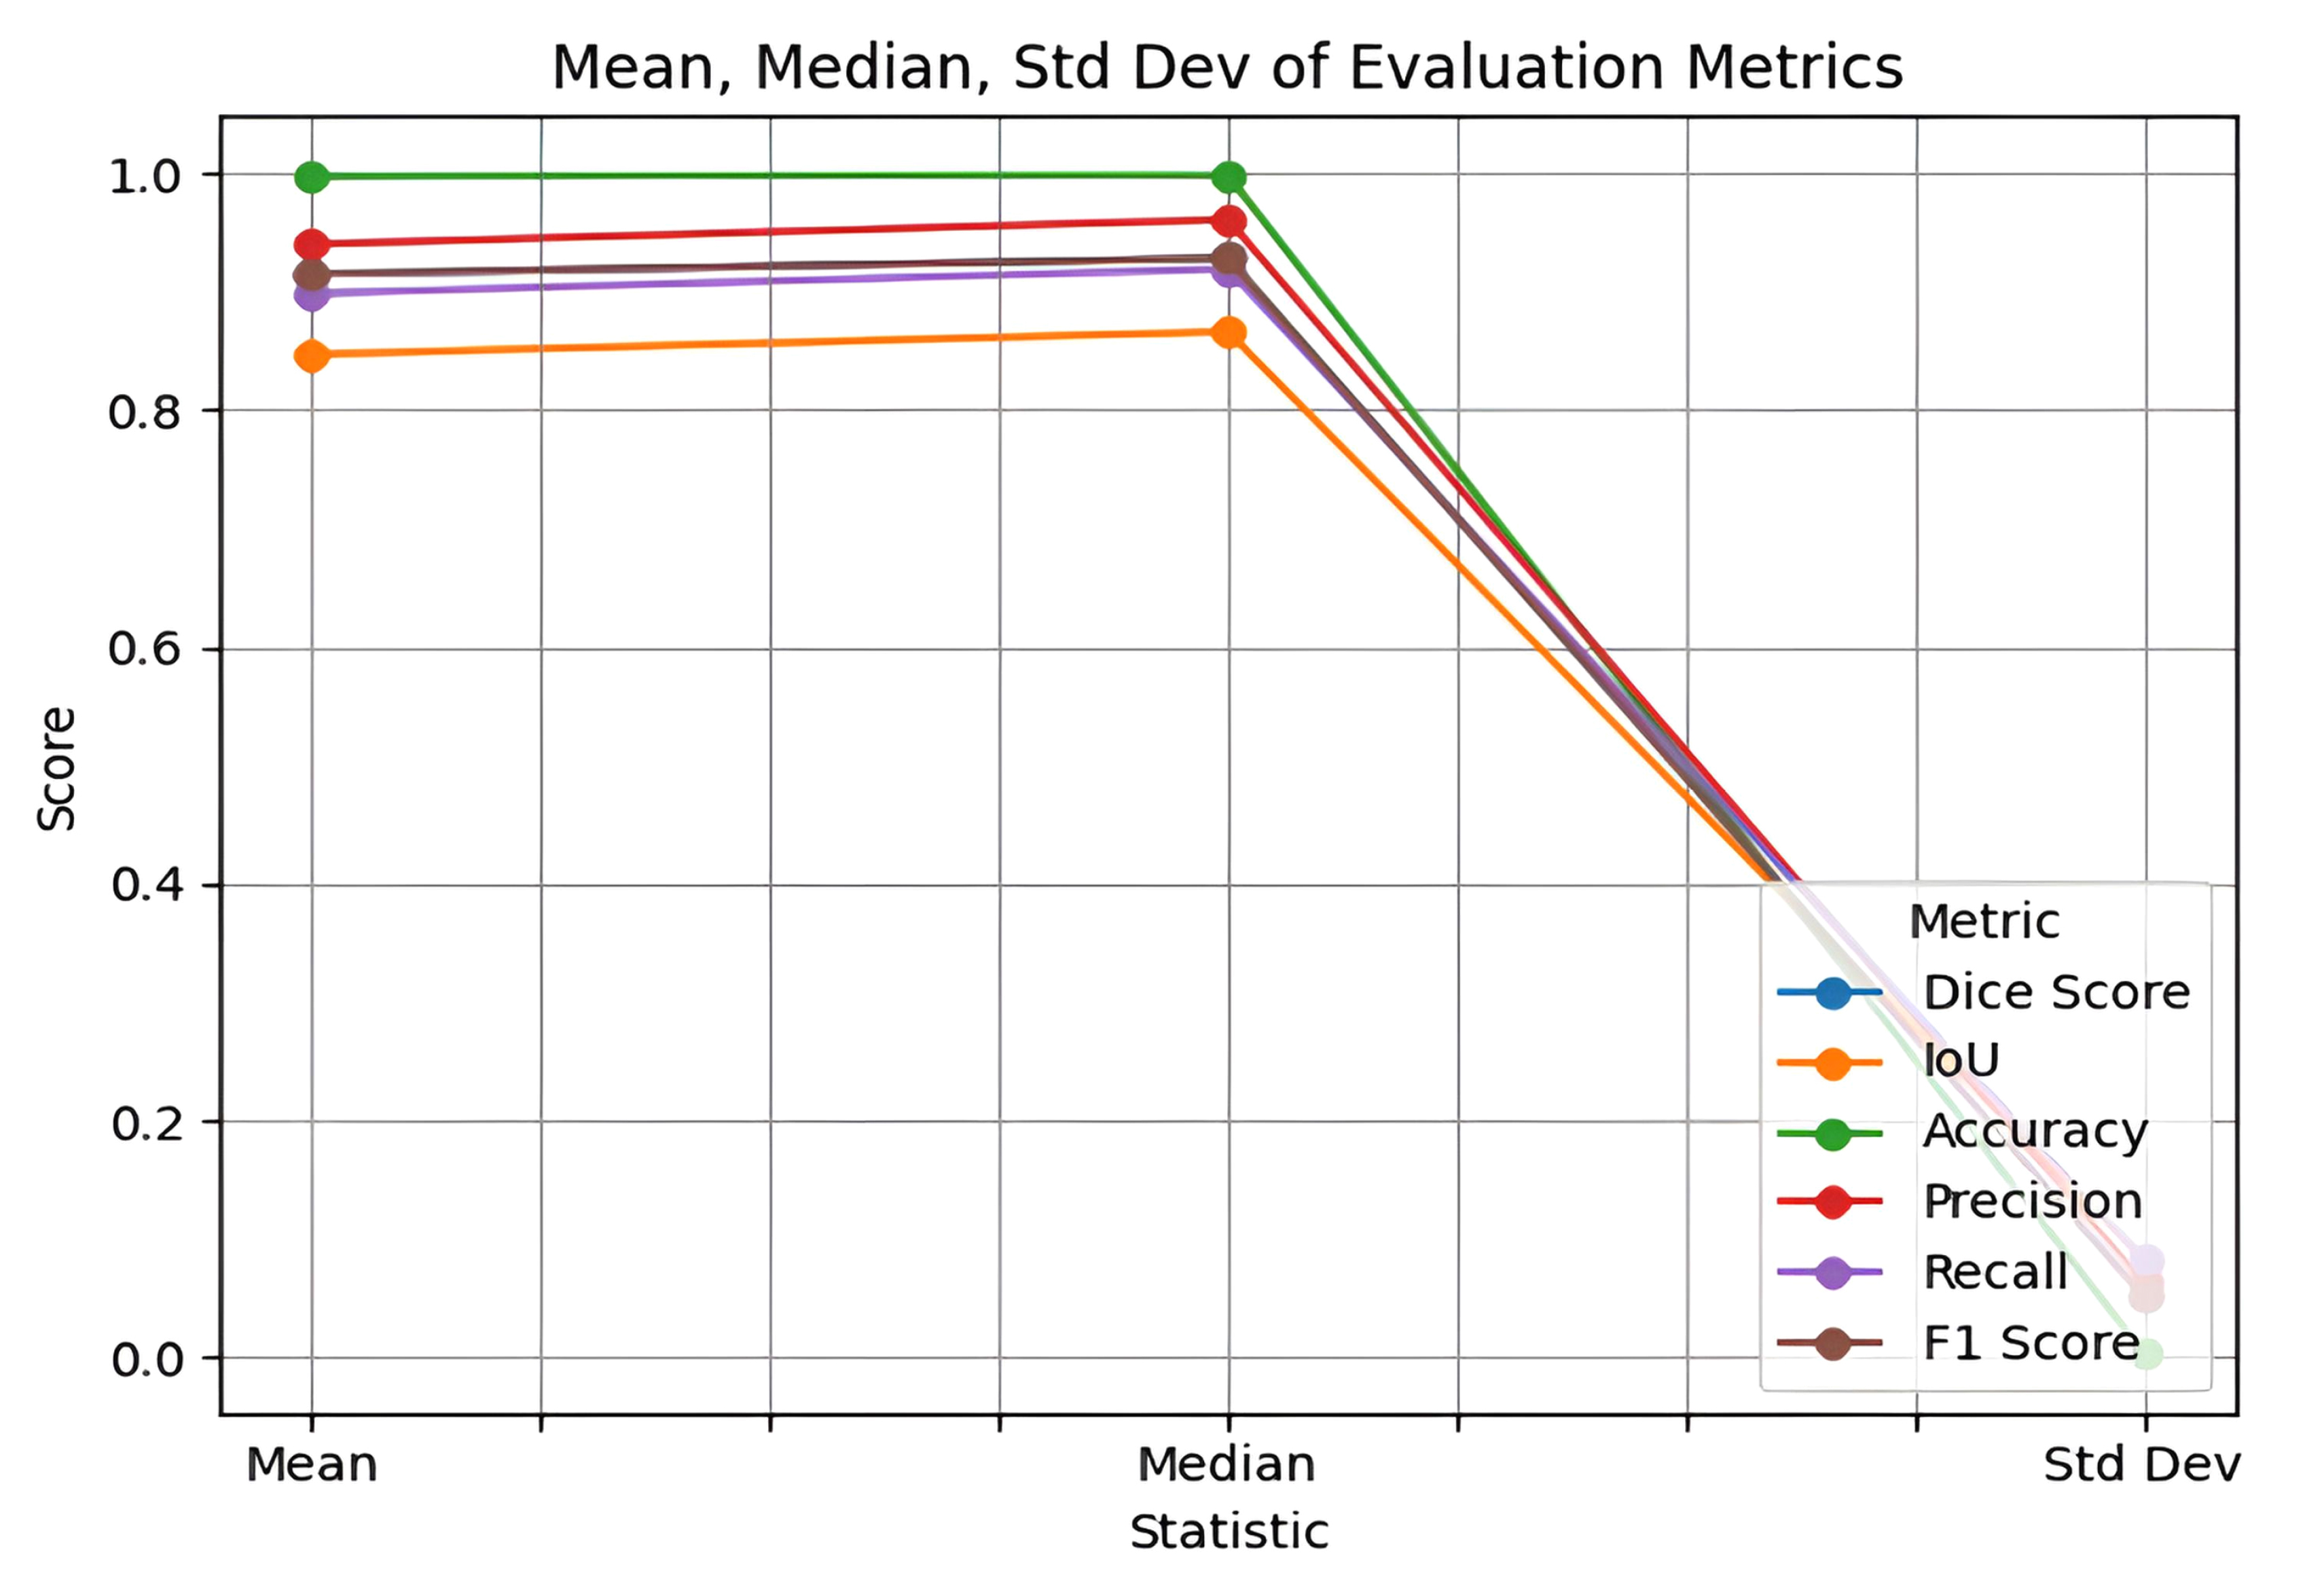

The results, obtained using a fixed split of 2,451 training images, 307 validation images, and 306 test images, show consistent performance across multiple evaluation metrics. In addition to accuracy and Dice coefficient, other measures such as precision, recall, F1 score, and IoU were also calculated and are presented with their mean, median, and standard deviation to reflect both central tendency and variability, as shown in Fig. (10). This comprehensive assessment confirms the robustness of the developed model and provides further confidence in its generalizability.

Mean, median, and standard deviation metrics of proposed model.